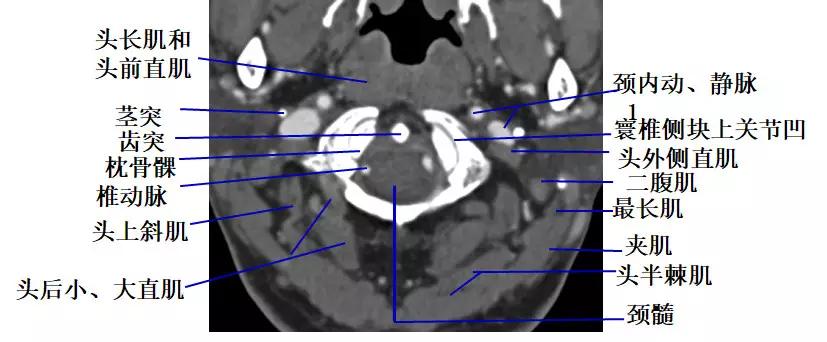

1. 经寰枕关节的横断层面(CT)